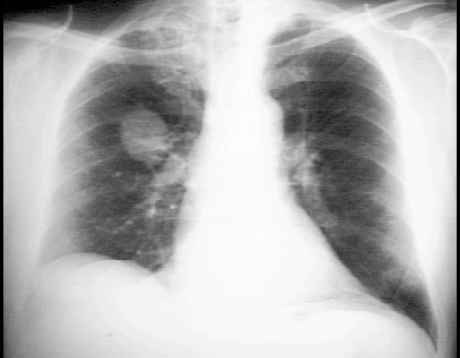

These chest X rays show a pulmonary lesion, or mass. In this PA view, a solitary lesion is seen in the right upper lobe. The mass shows no cavitation or calcification and should be considered cancerous unless proven otherwise. There is also asymmetry of the lung apices with pleural thickening and stranding on the right. This may be due to radiation or previous granulomatous disease such as tuberculosis. Tha cardiovascular structures are unremarkable. The lateral view also demonstrates the solitary lesion or mass in the peripheral portion of the anterior segment of the right upper lobe, with pleural thickening and stranding in the apex. The cardiovascular structures are, again, within normal limits.